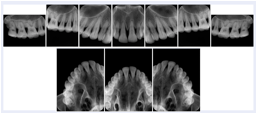

OO.1.4 Radiology

• A radiologist on his PACS assembles a screen layout of a stack of CT images of a current lung study, a secondary capture of a 3-D rendering of the CT, and a prior chest radiograph for the patient. He adjusts the window width / window level for the CT images, and zooms and annotates the radiograph to clearly indicate the tumor. He saves a Structured Display object representing that screen layout, including Grayscale Softcopy Presentation State objects for the CT WW/WL and the radiograph zoom and annotation. During the weekly radiology department conference, on an independent (non-PACS) workstation, he accesses the Structured Display object, and the display workstation automatically loads and places the images on the display, and presents them with the recorded WW/WL, zoom settings, and annotations.

• A mammographer reviews a screening exam on a mammo workstation. She wishes to discuss the exam with the patient's general practitioner, who does not have a mammo-specific workstation. She saves a structured display, with presentation states for each image that replicate the display rendered by the mammo workstation (scaling, horizontal and vertical alignment, view and laterality annotation, etc.).

Mammography Structured Display

Figure OO-7. Mammography Structured Display